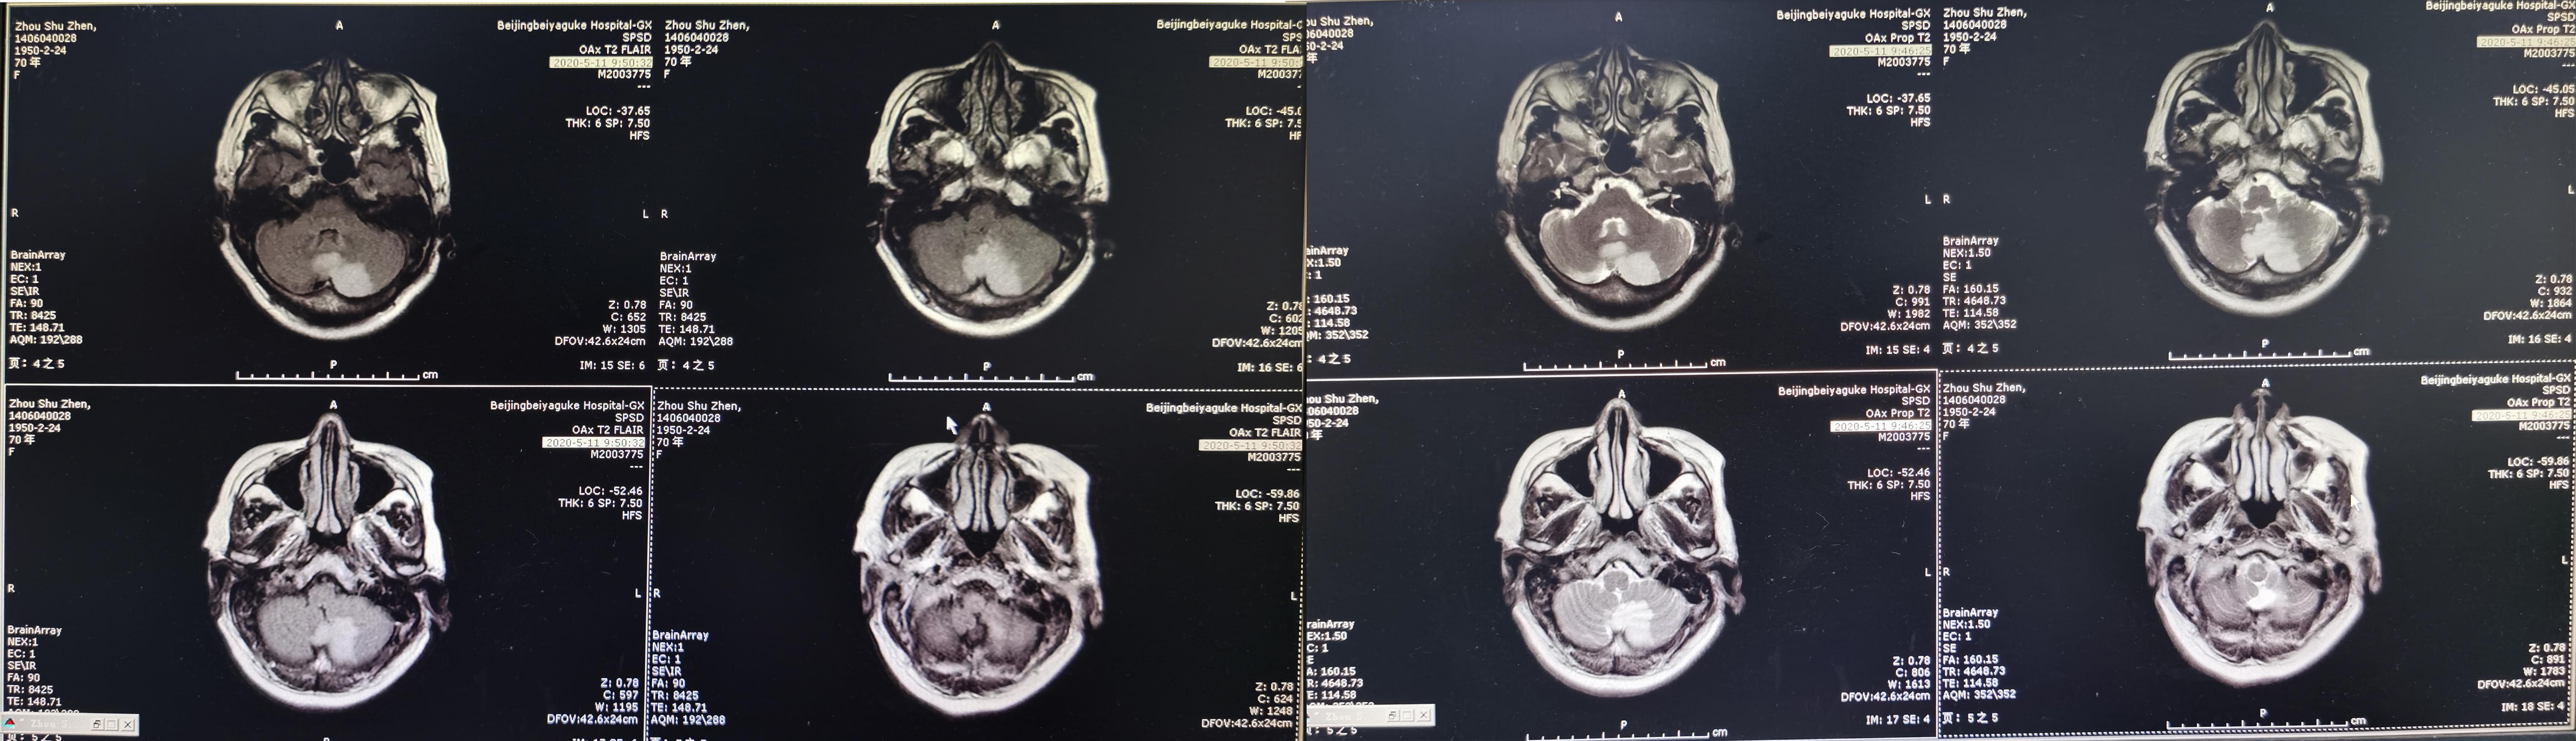

2020年5月10日(即第一次颈椎术后18天)患者洗脸时再次突发头晕,表现为天旋地转,恶心,呕吐视物旋转,行走不稳,经休息症状不缓解,再次就诊入院。查头颅MR显示急性小脑梗塞( 图-3 ),给予改善微循环、降血脂、控制血压及对症治疗后患者头晕好转出院,但行走时仍有摇晃感。

图-3: 2020年5月10日头颅MR